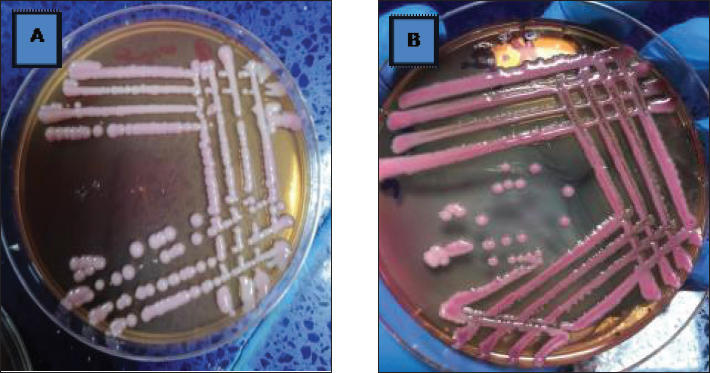

The current study demonstrated that Raoultella planticola exhibits mild pathogenicity when administered via the intranasal route in rabbits. The observed clinical signs (dullness, nasal and ocular discharge) and pathological findings (pulmonary emphysema) suggest that this bacterium can induce respiratory infection under experimental conditions. These et al findings align with Podschun (1998), who reported that Raoultella planticola is an environmental bacterium commonly found in water, soil, and plants, capable of colonizing humans and animals. The bacterium is a facultative anaerobic Gram-negative bacillus belonging to the Enterobacteriaceae family. It forms mucoid colonies on MacConkey agar due to polysaccharide capsule production (Figs. 1 and 2), making it morphologically and biochemically similar to Klebsiella spp. (Table 1).

Fig. 2. A Comparison between Colonies of klebsiella pneumonia (A) culturing on MacConkey agar which appear as mucoid dark pink colony and Colonies of Raoultella planticola (B ) culturing on MacConkey agar appear as mucoid pink colonies Table 1. VITEK2 result show presence of Raoultella planticola.

Fig. 6. Group of infected rabbits lung (A) Bronchiols show emphysema aggregation of lymphocytic cell (black arrow)( B) show emphysema structure atelectasis (black arrow) H&E stain 400X and lung H&E stain 200X. Gross examination of sacrificed animals (group of infected rabbits) showed hemorrhage in the upper respiratory tract (Fig. 3). The trachea exhibited a semi-circular hyaline cartilage structure (Fig. 4), and the bronchi branched into left and right bronchioles, consistent with typical mammalian respiratory anatomy. Normal histological details of trachea of control group• Tunica mucosa • Tunica submucosa • Tunica adventitia • C-shaped hyaline cartilage (Fig. 5A) • score lesion of Pathological Changes • Emphysema was observed in 3 out of 5 cases (60%) (Fig. 4). • No pathological changes were seen in 2 cases (40%). • Vascular changes, including congestion, thrombosis, and alveolar hemorrhage, were noted in 10% of affected cases. Comparative morphologyLight microscopy analysis confirmed Gram-negative rods for Raoultella planticola. However, differentiation from Klebsiella spp. was challenging due to morphological similarities (Fig. 2A and B). The histological findings of emphysema and atelectasis align with Blagojević et al. (2018), who described similar structural changes in respiratory infections. The observed hemorrhage and vascular congestion support Castro et al. (2001), who linked these changes to bacterial-induced trauma. The 60% incidence of emphysema suggests that Raoultella planticola primarily induces chronic obstructive pulmonary disease (COPD)-like lesions, differing from Sarhad (2011), who reported fibrinous pleuropneumonia as the dominant pathology. This discrepancy may stem from differences in infection routes or host susceptibility. The short respiratory passage and direct bronchial branching in rabbits (Abdelsalam and Al Sadrani, 2015) likely contribute to higher lung infection rates. Additionally, the similarity between Raoultella and Klebsiella (Alampoondi Venkataramanan et al., 2021) complicates microscopic differentiation, necessitating advanced diagnostic methods like Vitek2.Contrary to Vinshia, J. J., (2024), this study found no fibrinous bronchopneumonia, instead emphasizing edema and congestion (Das and Bhagman, 1997). The reclassification of Raoultella from Klebsiella prior to 2001 further underscores the need for precise microbiological identification (Fig. 8). This study highlights Raoultella planticola's potential to cause respiratory pathology, warranting further investigation into its zoonotic risks.